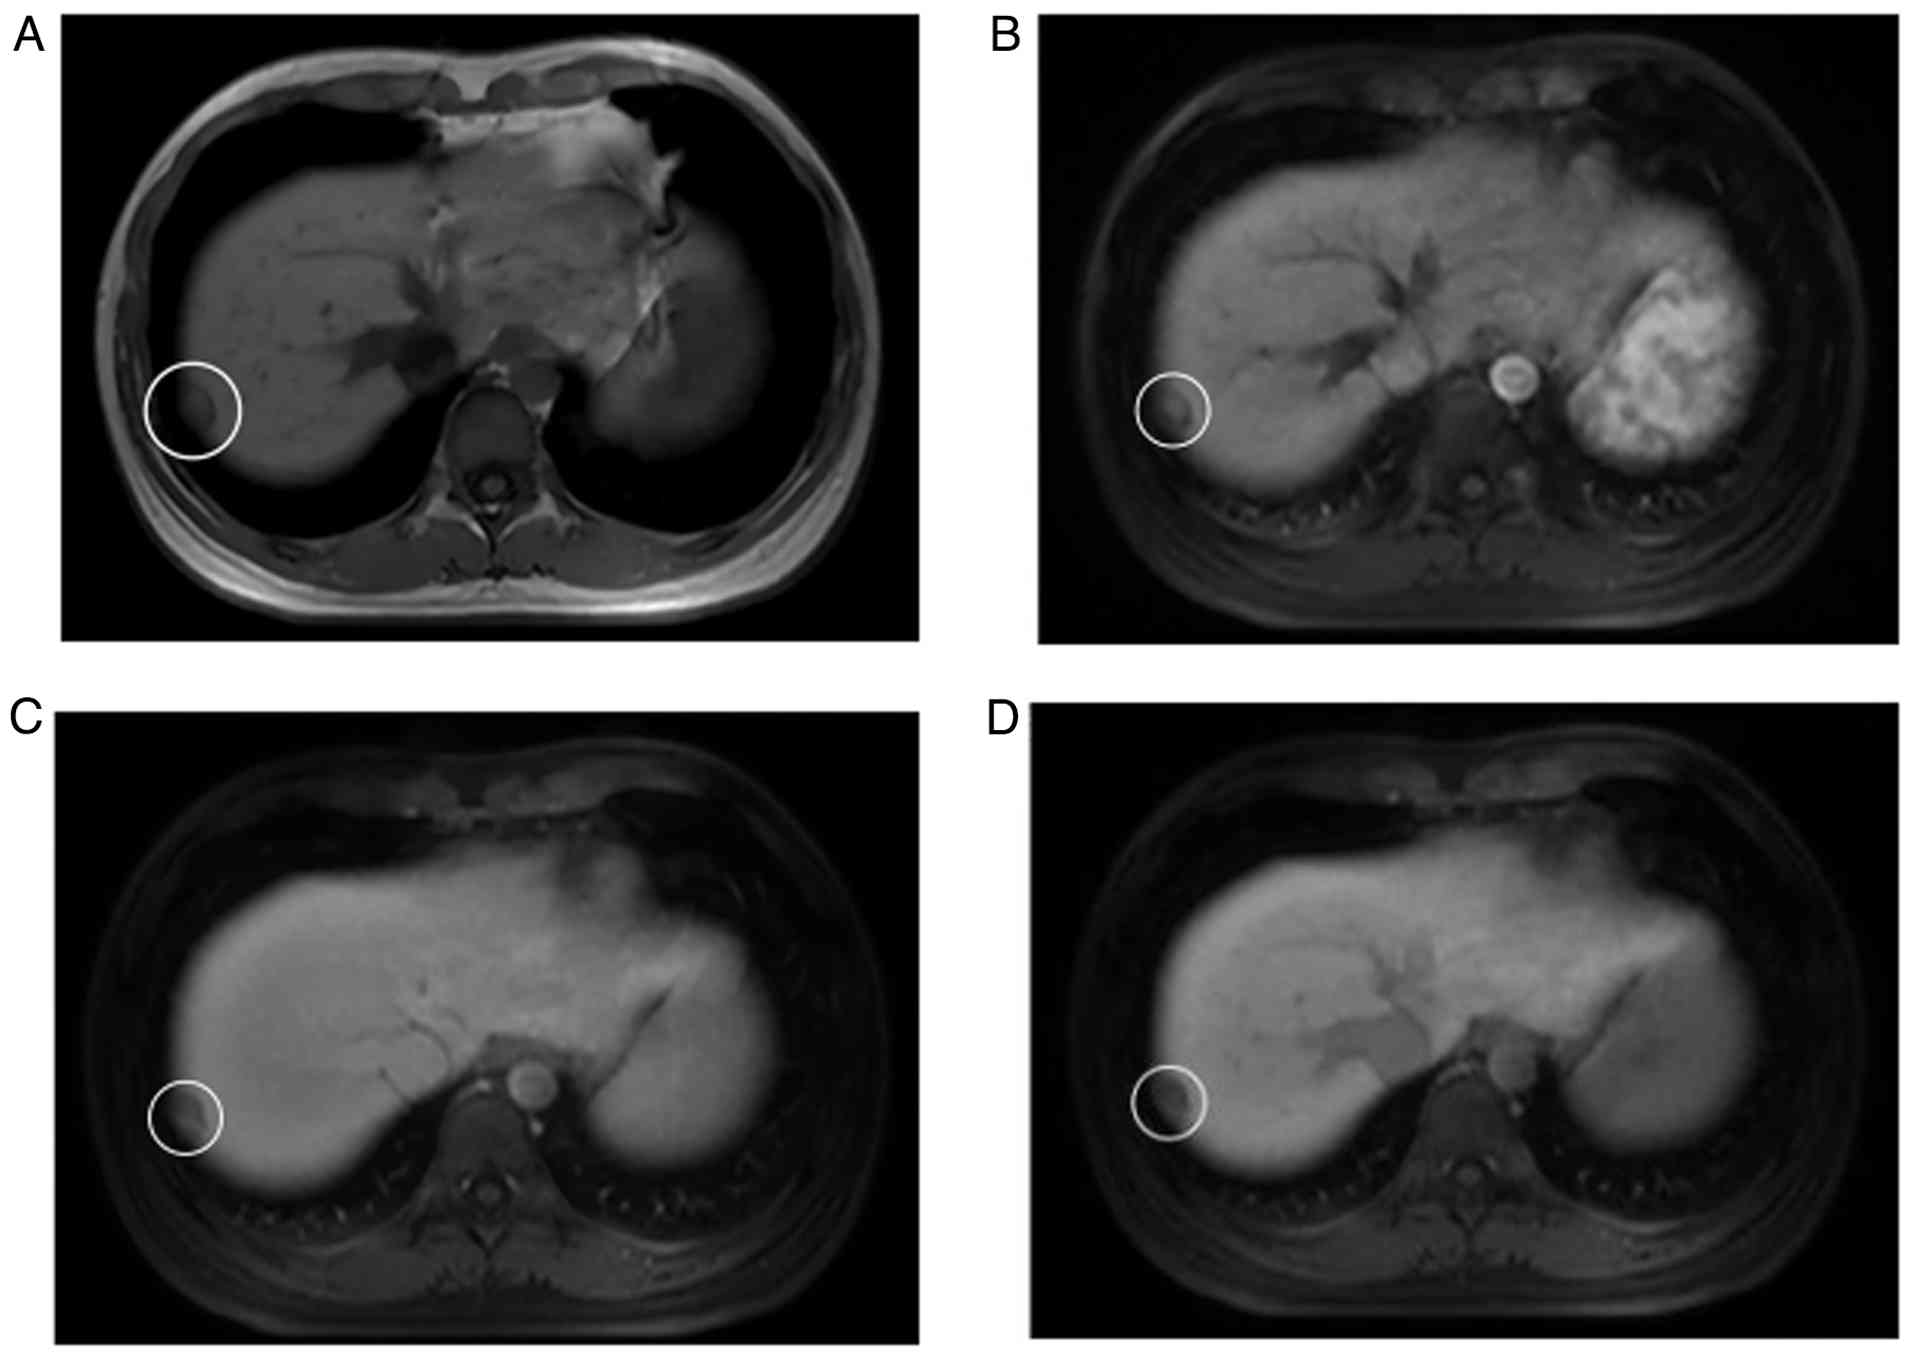

In November 2021, prior to planned further systemic treatment, a follow-up abdominal MRI showed a newly detected subcapsular nodule (18×10 mm) in segmen 7 (S7) of the liver. On T1-weighted imaging, it presented as a slightly hypointense signal lesion (Fig. 2A). Contrast-enhanced scanning showed mild heterogeneous enhancement, and there was no contrast agent uptake during the hepatobiliary-specific phase, which was diagnosed as intrahepatic metastasis (Fig. 2B-D). Subsequently, the patient was administered a combination therapy of lenvatinib (8 mg once daily) and toripalimab (240 mg).

At 1 month after resection of the

primary tumor of liver segment S6, MRI findings were as follows:

(A) As shown by the white circle, the hepatic nodule in segment 7

presents with a slightly hypointense signal on T1-weighted imaging

and an annular hypointense capsule is observable. (B) In the

arterial phase of contrast-enhanced scanning, the lesion manifests

with mild heterogeneous enhancement without capsular enhancement.

In the (C) portal venous and (D) delayed phase, the extent of

enhancement diminishes.

Figure 2.

At 1 month after resection of the primary tumor of liver segment S6, MRI findings were as follows: (A) As shown by the white circle, the hepatic nodule in segment 7 presents with a slightly hypointense signal on T1-weighted imaging and an annular hypointense capsule is observable. (B) In the arterial phase of contrast-enhanced scanning, the lesion manifests with mild heterogeneous enhancement without capsular enhancement. In the (C) portal venous and (D) delayed phase, the extent of enhancement diminishes.